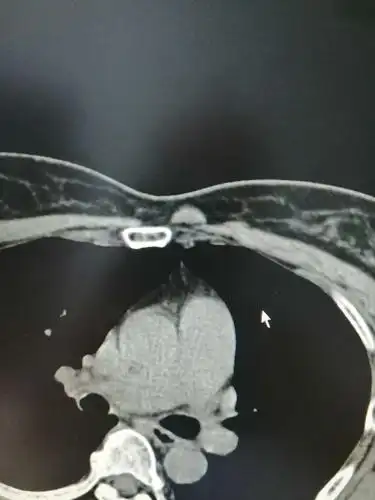

女性,54岁,胸骨柄突起畸形数年,偶尔疼痛